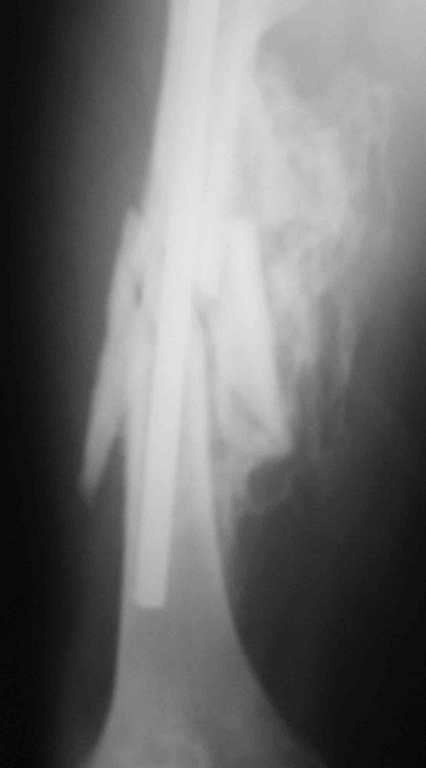

Re: 32- летний пациент с переломами обоих бедер после неудачного оперативного и консервативного лечения.

Иллюстрации к сообщению

Уважаемый Антон.Исходя из Вашего материального положения!! и наличия хорошего, грубого омозоления, равности длины конечностей и судя по снимкам не очень выраженной антекурвации, но выраженной контрактуры коленных суставов: чтоб не упустить время разработки суставов и активизировать больного, необходимо справа удалить стержень, рассверлить канал и произвести ЗИМО более толстым неблокир. стержнем т.к. на этом уровне можно получить устойчивый остеосинтез, после чего активизировать и дозированная, упорная ЛФК, а дальше после восстановления функции ,время покажеть.

Cyдя по представленным рентгенограммам оба бедра консолидированы. Необходима активная разработка движений в коленных суставах. Хотелось бы увидеть фотоснимки больного ( нижних конечностей спереди и сбоку). Если стержень мешает разработке движений то его надо удалить.

О происхождении такого запущенного случая- мой коллега работает экспертом ВТЭК и тянет в отделении и не такие казусы. Сегодня была сделана операция удален стержень из бедра и установлен стержневой аппарат из 2 опор, слева подвижности не наблюдалось, продолжается ЛФК. При необходимости позднее будет выполнена надмыщелковая корригирующая остеотомия. Спасибо всем за советы.